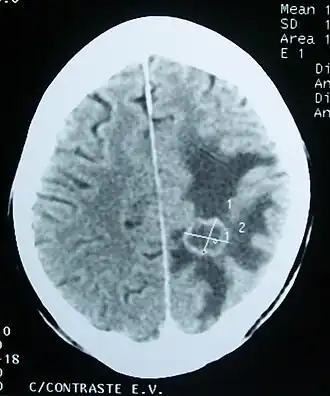

![]() Отёк вещества головного мозга (тёмный участок) вокруг метастатической опухоли (компьютерная томограмма) | |